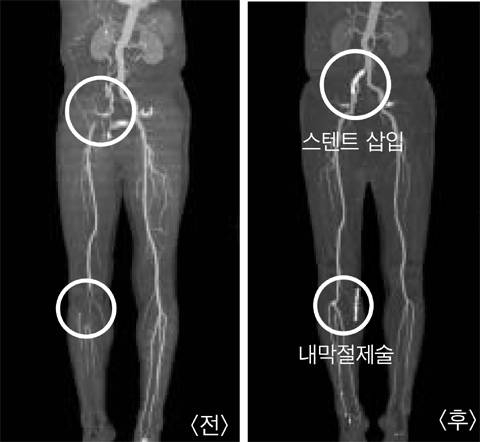

병원에 가면 혈관 CT(컴퓨터단층촬영)나 MRI(자기공명영상촬영)로 어느 위치의 혈관이 얼마나 막혔는지 정확히 찾는다.

혈관이 꽉 막히지 않고 통증이 심하지 않으면 아스피린을 복용한다. 약을 먹으면서 담배를 끊고 꾸준히 운동하며 혈압·혈당을 관리하면, 상당수가 증상이 완화된다. 이 치료로 호전되지 않으면, 스텐트삽입술(금속망을 좁아진 혈관에 넣어서 넓힘)이나 내막절제술(막힌 혈관의 내막을 긁어내 뚫어줌), 혈관우회술(막힌 동맥 사이에 인조혈관 등을 붙여 새 길을 냄) 등의 치료를 한다. 이렇게 치료해도 막혔던 곳의 위치에 따라 5~70%는 5년 안에 재발하기 때문에, 금연·저지방식·운동 등 올바른 생활 습관을 유지하는 것이 필수적이다.